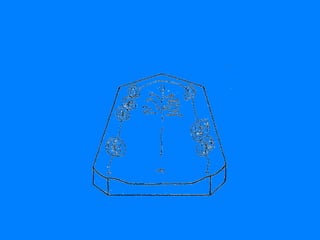

EFECTO DE ARCO  CRUZADO MUCOSO ESTE SE LIMITA UNICAMENTE A LA POSIBILIDAD QUE PUEDEN BRINDAR EL PALADAR Y LOS REBORDES RESIDUALES ( ARCO MAXILAR )  Y  ( ARCO MANDIBULAR ) DE COLABORAR EN LAS FUNCIONES DE SOPORTE Y ESTABILIDAD, YA QUE LA FUNCION DE RETENCION EVITANDO EL DESALOJO DE LA RESTAURACION PARCIAL REMOVIBLE ES UNA FUNCION  BASICA   DE LOS DIENTES PILARES.

CLASE I LIMITACION 14-24   DOBLE EFECTO DE ARCO CRUZADO REBORDES RESIDUALES Y PALADAR EFECTO DE ARCO CRUZADO MUCOSO CLASE I LIMITACION 34-44 DOBLE EFECTO DE ARCO  CRUZADO REBORDES RESIDUALES